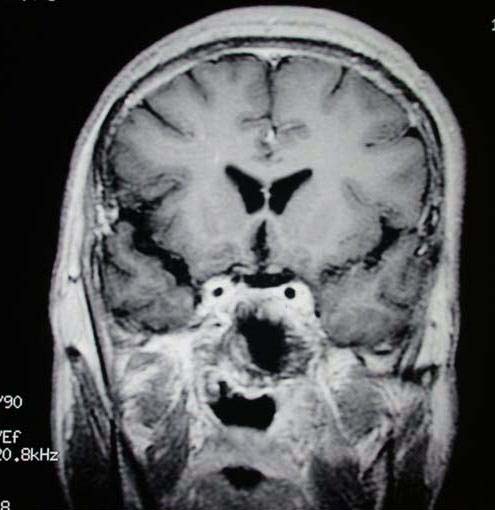

术后